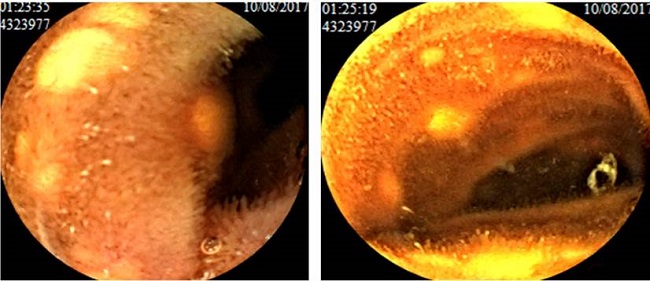

Así pues, se ordenó realizar una endoscopia de vía digestiva alta (EVDA) y una colonoscopia, como parte del estudio del dolor abdominal. En la colonoscopia, solo identificamos hemorroides internas grado II, mientras que en la EVDA reportamos múltiples inclusiones amarillentas, submucosas, de, aproximadamente, 3 mm cada una (Figura 1), localizadas en el duodeno, hasta el ángulo de Treitz.

Además, se tomó una biopsia que reportó la existencia de células de tejido adiposo maduro. Por tanto, se decidió realizar una videocápsula endoscópica, a fin de determinar de forma más precisa la extensión de las lesiones. El estudio mostró múltiples lesiones amarillentas, de diferente tamaño, de aspecto benigno y con características similares a las reportadas en la EVDA, en todo el intestino delgado hasta la válvula ileocecal (Figura 2).